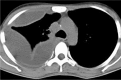

A pleural effusion is an excessive accumulation of fluid in the pleural space. It can pose a diagnostic dilemma to the treating physician because it may be related to disorders of the lung or pleura, or to a systemic disorder. Patients most commonly present with dyspnea, initially on exertion, predominantly dry cough, and pleuritic chest pain. To treat pleural effusion appropriately, it is important to determine its etiology. However, the etiology of pleural effusion remains unclear in nearly 20% of cases. Thoracocentesis should be performed for new and unexplained pleural effusions. Laboratory testing helps to distinguish pleural fluid transudate from an exudate. The diagnostic evaluation of pleural effusion includes chemical and microbiological studies, as well as cytological analysis, which can provide further information about the etiology of the disease process. Immunohistochemistry provides increased diagnostic accuracy. Transudative effusions are usually managed by treating the underlying medical disorder. However, a large, refractory pleural effusion, whether a transudate or exudate, must be drained to provide symptomatic relief. Management of exudative effusion depends on the underlying etiology of the effusion. Malignant effusions are usually drained to palliate symptoms and may require pleurodesis to prevent recurrence. Pleural biopsy is recommended for evaluation and exclusion of various etiologies, such as tuberculosis or malignant disease. Percutaneous closed pleural biopsy is easiest to perform, the least expensive, with minimal complications, and should be used routinely. Empyemas need to be treated with appropriate antibiotics and intercostal drainage. Surgery may be needed in selected cases where drainage procedure fails to produce improvement or to restore lung function and for closure of bronchopleural fistula.